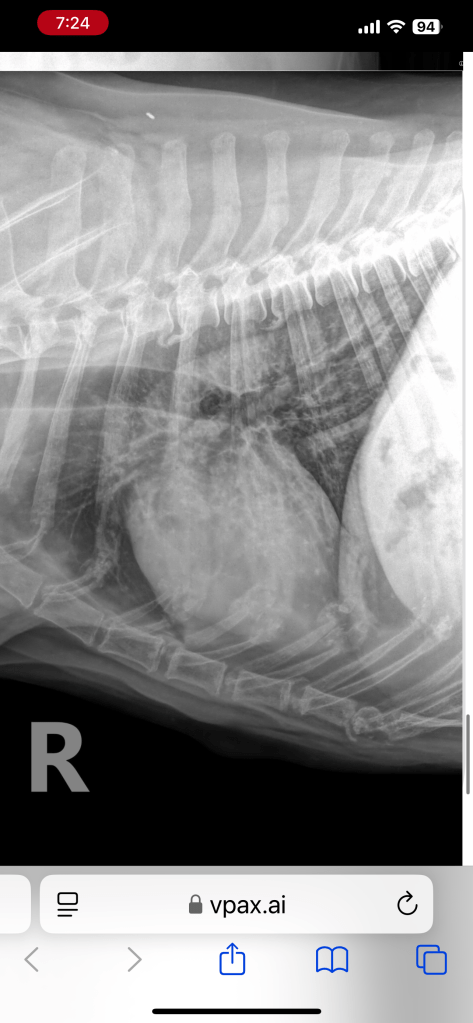

my baby left us at 13 years young. He had a cancer scare (Hemangiosarcoma) July 2024 and collapsed huffing and puffing into my arms. Closed his little beady eyes and rested his entire heads weight in my arms. Lost bowel control. I was so scared. But he got up. Puked. Swam. Slept all night and the next day was doing better. After an er vet visit where the vet said he had bleeding cancer, we got to work. Plenty of chinese yunnan baiyao herbs to stop bleeding. Gabapentin for any pain. In that time we camped with alpacas in Lebec, visited beaches, stayed in San Luis Obispo, played with young rattlesnakes in San Diego mountains and he ate like a king. Organic everything. Steaks. Fish. Shrimp. Crayfish. Crab. Scallops. All with the best specialty olive oil and kale/broccoli. He got in lots of swims lots of walks (he was arthritic so I had to hoist his weight using harness). His mommy and I made sure his remainder life was the best.